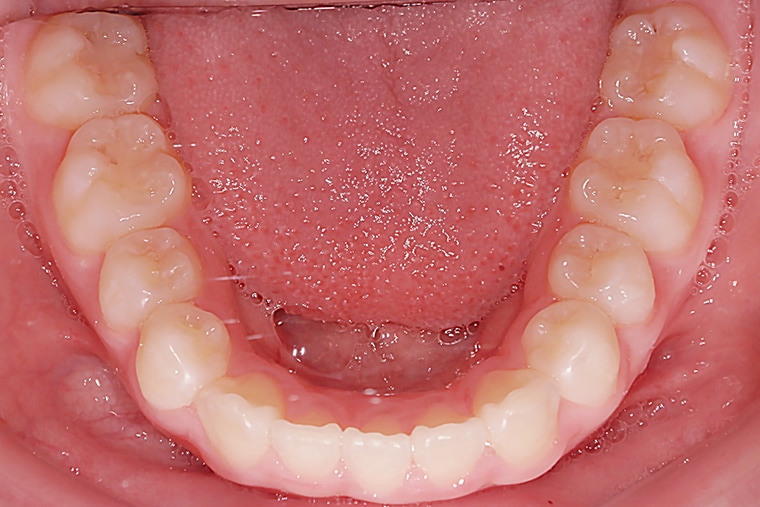

AFTER

約10ヶ月の矯正期間を経て、上の前歯の出っ歯は改善され、口を閉じることが自然にできるようになりました。歯並びが整ったことで笑顔に自信が持てるようになり、日常生活でも以前より表情が明るくなったのを感じます。学校生活や友達との会話でも、口元を気にすることが少なくなり、本人も嬉しそうです。